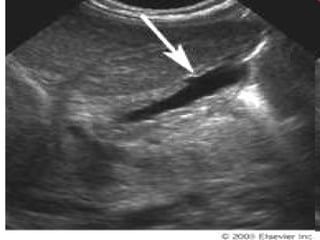

MR

cholangiogram

Images obtained in a 57-

day-old female infant with

cholestatic jaundice .

Transverse power Doppler

US image of the liver shows

a tubular cystic lesion

(straight arrow), which does

not have a flow signal,

anterior to the portal vein

(curved arrow). Cursors

indicate the maximum depth

of this cystic lesion

MR cholangiogram Images obtained ina 57- day-old female infant with cholestatic jaundice . Transverse power Doppler US image of the liver shows a tubular cystic lesion (straight arrow), which does not have a flow signal, anterior to the portal vein (curved arrow). Cursors indicate the maximum depth of this cystic lesion